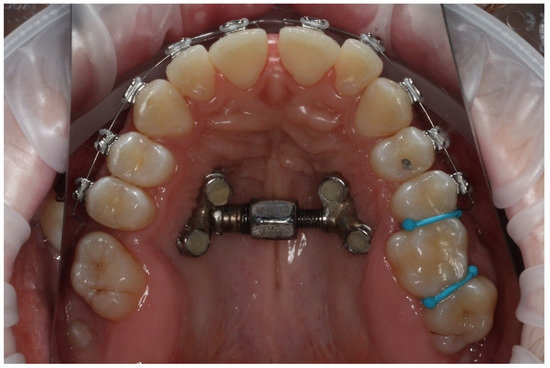

- Following cone beam computed tomography (CBCT) examination and analysis of the intended location of the mini-implant, the temporary orthodontic implant screws were inserted under local anesthesia. Dual-Top JS jet screw implants (Tiger Dental, Bregenz, Austria) with a diameter of 2.5 mm were used. Four implants were inserted in each patient: two mesially and two distally. Depending on the amount of bone available, implants of 12, 14, or 16 mm in length were inserted by the same operator (BWL).

- After two weeks of the healing, an alginate impression with transfers caps was taken. A master cast was produced in the in-house laboratory from Class IV plaster with four laboratory analogues. The distractor size was chosen based on the clinical situation (the available screw body sizes were 8 mm, 10 mm, 12 mm, 14 mm, and 16 mm). We refer to the appliance as the PS4 Distractor, after the Power Screw (PS) and the number of implants on which it was placed. The master cast with the selected screw and four collars for adhesive bonding was sent to the laboratory. All distractors were made in the same laboratory (Ortolab, Częstochowa, Poland).

- After a further three weeks, the distractor was cemented onto the implants using SDI Riva Self Cure HV Glass Ionomer (Melbourne, Australia) cement by the same operator (BWL). An example is presented in Figure 1.

- The patient (or the patient with his or her parents) was instructed on how to deal with the distractor as follows: The screw should be turned twice daily, in the morning and the evening. Each screw has six surfaces, each of which should be counted when turning. Each surface is marked with one, two, or three black dots for visual saliency. A full turn of the screw would result in an expansion of 1 mm, whereas turning the screw by one sixth of a full rotation (one surface) would give an expansion of 0.17 mm. A Power Screw open-ended spanner is used to turn the screw, with the correct direction of rotation being from the upper to the lower incisors. The patient should open the mouth as widely as possible, placing the spanner on the hexagon of the screw body so that the handle is near the upper front teeth. The spanner should then be turned until it is positioned just before the lower teeth (on the tongue). The spanner should then be detached, turned 180° around the longitudinal axis, and placed back on the upper teeth; it should then be moved downwards again, as shown in Figure 2.